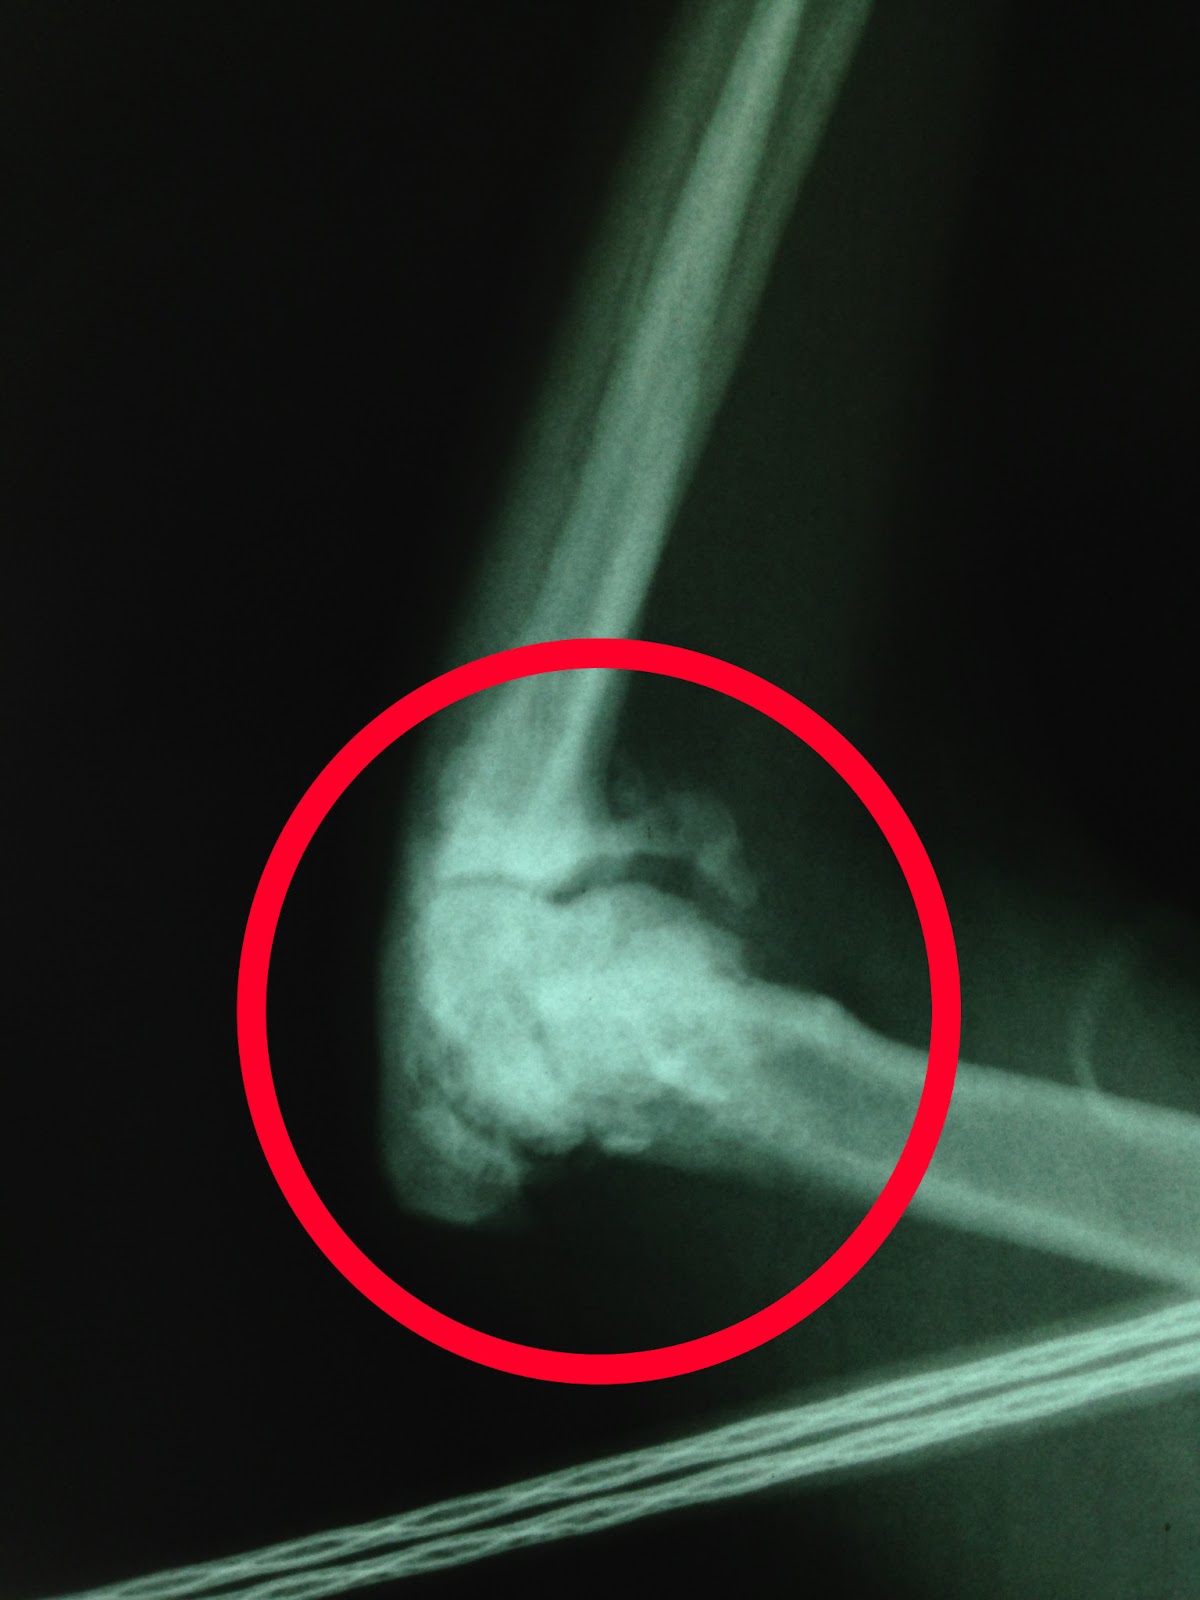

Surgical treatment of traumatic elbow Luxation in a Cat

Dislocated elbow in a cat DV view Veterinary tech, Veterinary Why Is My Cats Elbow Swollen Swelling is an external sign of an internal. Holding leg so paw does. Signs of osteoarthritis include lameness, joint swelling, wasting away of muscle, thickening and scarring of the joint membrane, and a grating. Listed below are some of the signs they may. Possible causes of joint swelling in cats include injury, disease, or congenital malformation. The following symptoms are. Why Is My Cats Elbow Swollen.